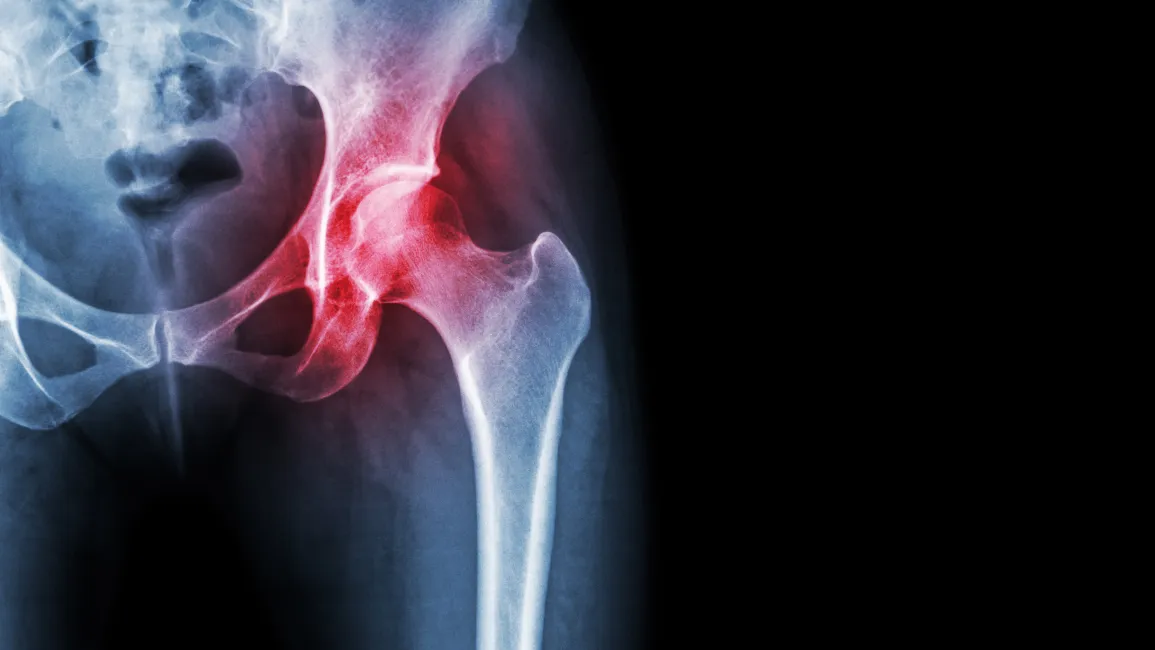

With the rapidly expanding field of regenerative medicine, hip pain patients now have a more effective and conservative alternative to total joint replacement surgery. Human tissue allograft injections are offering those with severe or even bone-on-bone osteoarthritis new options. Treatments have provided symptom relief and improved function for many degenerative arthritis patients. Allograft joint injections to the hip joint are also highly effective for acute conditions such as bursitis and even labral tears.

Regenerative medicine  is the best alternative to surgery providing strong anti-inflammatory effects while still stimulating the body to repair damaged tissue. Unlike surgery, this state-of-the-art treatment has no dangerous adverse effects and requires no downtime

Regenerative medicine is the best alternative to surgery providing strong anti-inflammatory effects while still stimulating the body to repair damaged tissue. Unlike surgery, this state-of-the-art treatment has no dangerous adverse effects and requires no downtime.

The progression of degeneration in the hip joint is the cause of most chronic hip pain. Although the symptoms may be very insidious at first, the process of degeneration typically takes many years to develop. If not addressed, this degeneration results in bone-on-bone deterioration and the eventual total joint replacement of the hip. In many cases, symptoms do not become severe until near the end stages. This typically means that many arthritis hip pain patients do not seek treatment or get x-rays until it is too late.